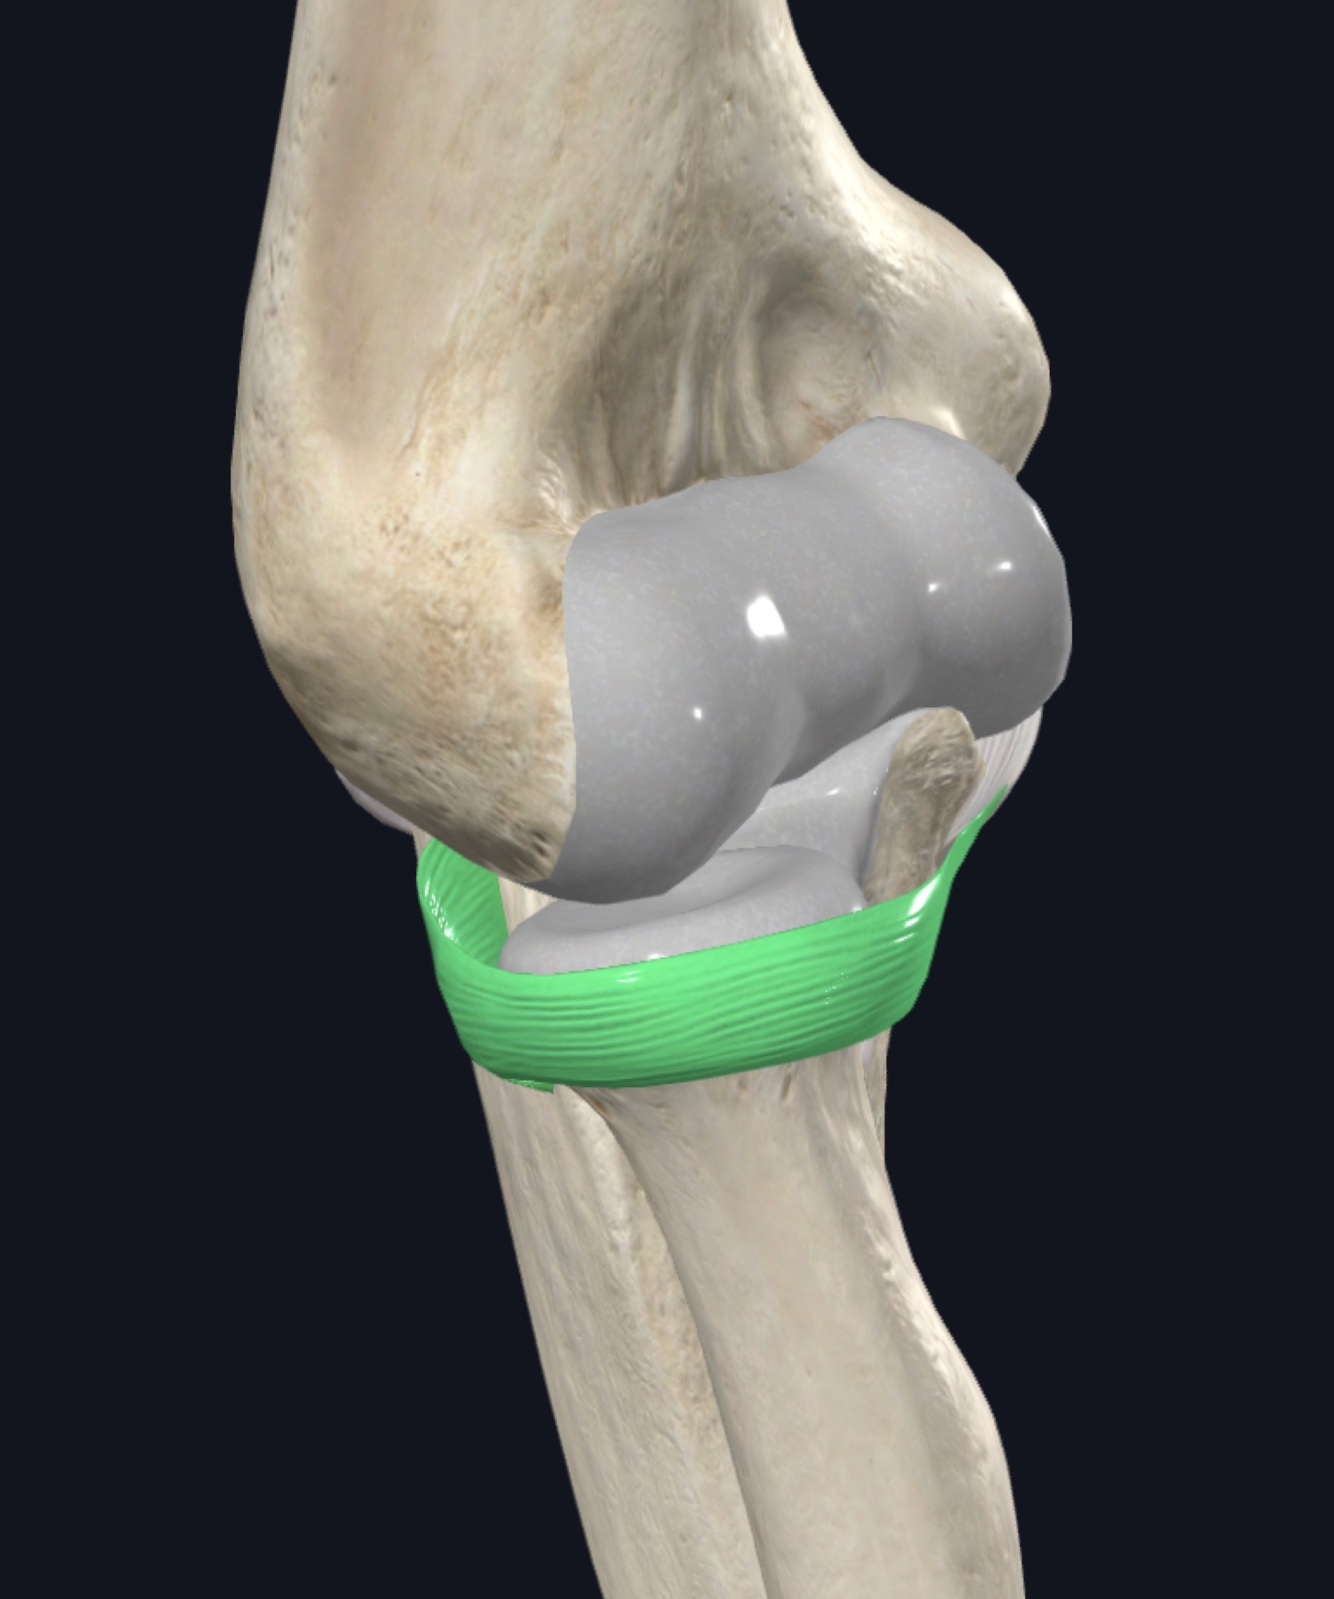

What are the components of the annular ligament? Its attachments?

Superior & inferior oblique bands

Annular ligament band itself

Attachments: anterior and posterior portions of the sigmoid notch of the proximal radius